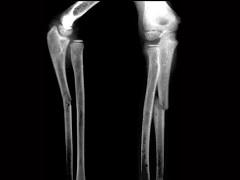

男,7岁,肘部外伤,根据所示图像,最可能的诊断是?(?)A.尺骨中上段骨折B.桡骨小头脱位C.孟氏骨折D.盖氏骨折E.以上均不正确

问题 男,7岁,肘部外伤,根据所示图像,最可能的诊断是?(?)

选项 A.尺骨中上段骨折 B.桡骨小头脱位 C.孟氏骨折 D.盖氏骨折 E.以上均不正确

答案 C